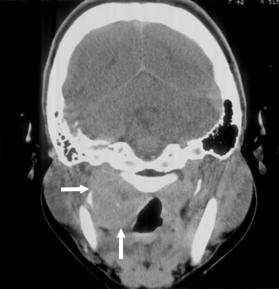

【108-1 醫學(六) 第72題】

21歲男性因上頸部硬塊求診,接受對比劑注射後的電腦斷層掃描如圖⽰,則最可能診斷為何?